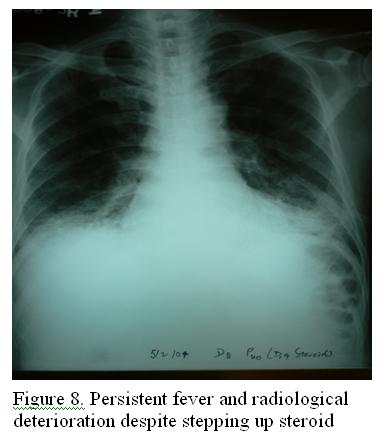

Despite these treatment, there was still intermittent fever, with both radiological and respiratory worsening (Figure 8). Fibreoptic bronchoscopy and bronchioalveolar lavage (BAL) was performed , which found pneumocystis carinii (PCP); cytomegalovirus (CMV) early antigen detection was positive from BAL and CMV pp65 antigenaemia showed 1 pos/ 2×105 WBC. Standard intravenous septrin therapy was given and steroid continued for PCP infection. Followed by septrin prophylaxis and steroid tapering in the subsequent 3 weeks. Apparently, the clinical condition improved . Malignancy screening including nasal biopsy, Epstein bar virus (EBV)-IgA, alpha fetal protein, carcinoembryonic antigen, prostate specific antigen and carbohydrate antigen 19.9, CT abdomen and pelvis were all negative.